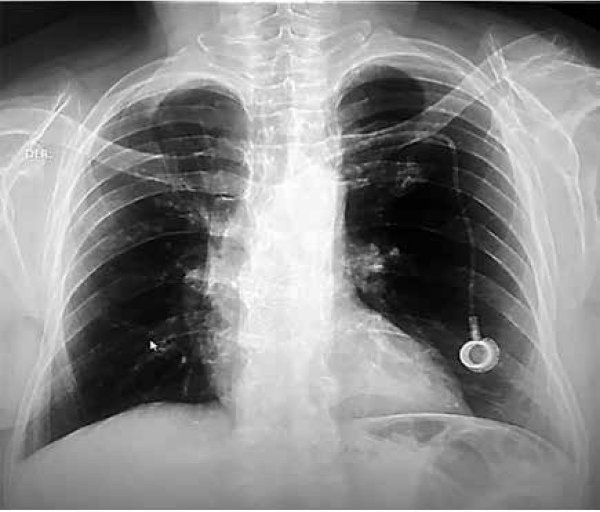

Se realizó también RX PA de tórax de control con cardiomegalia grado I, crecimiento ventricular izquierdo, aorta desenrollada, datos de aortoesclerosis, hilios con ligera congestión e hiperflujo pulmonar moderado, se evidencia catéter de quimioterapia (FIGURA 3).